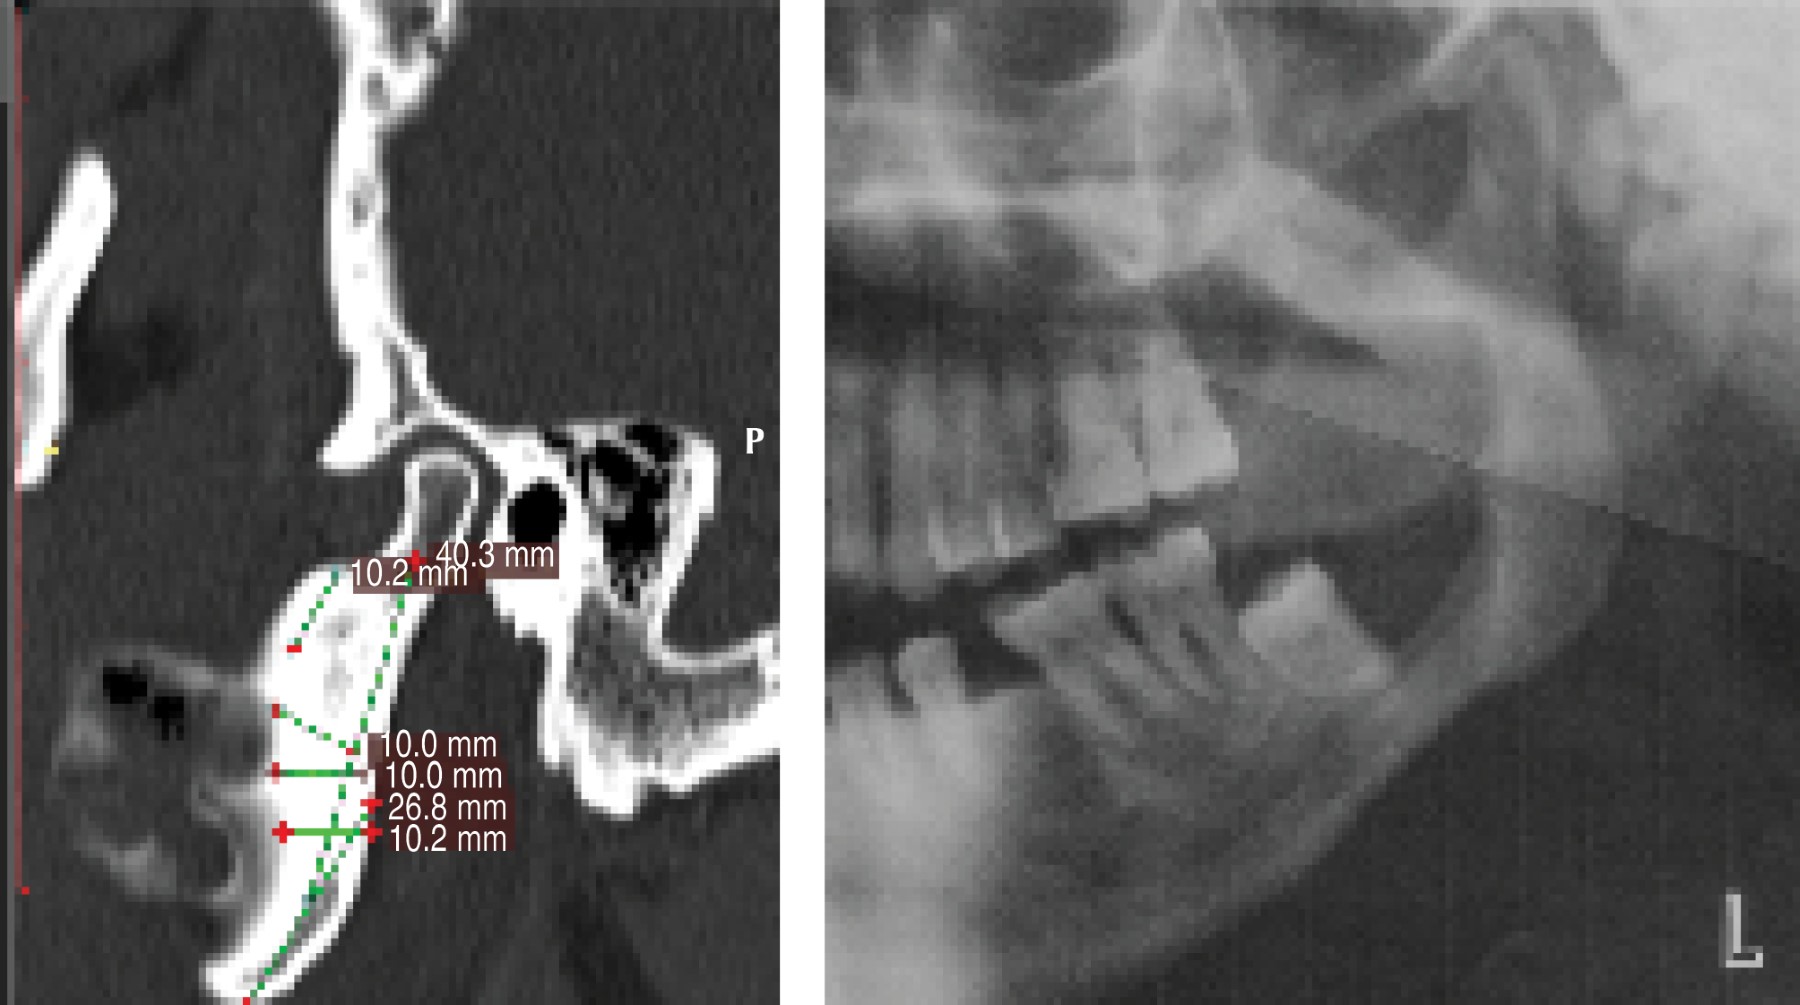

En enero de 2014 un paciente de 50 años de edad concurre al Servicio de Cirugía Maxilofacial del Hospital Zonal General de Agudos Manuel Belgrano presentando asimetría facial a causa de aumento de volumen en región geniana del lado izquierdo (Figura 1) con un estudio anatomopatológico con resultado de ameloblastoma multiquístico folicular en maxilar inferior. Como antecedente médico relevante el paciente padece diabetes tipo II. Se hicieron los estudios por imágenes de rutina (Figura 2) y en mayo de 2014, luego de firmar el consentimiento informado, se le realizó la resección segmentaria mandibular con un margen de seguridad de 1.5 cm, el cual permitió conservar el cóndilo mandibular, y se efectuó la reconstrucción inmediata con una placa de reconstrucción TMS 2.4 (WL, BIOMET) (Figura 3).

En agosto de 2015 se planificó la reconstrucción simultánea del componente mandibular y articular (Figura 5). A partir de este diseño se confeccionó una prótesis aloplástica personalizada Lorenz-Biomet (Biomet Microfixation, Jacksonville, FL, USA).

Figura 2

Figura 3